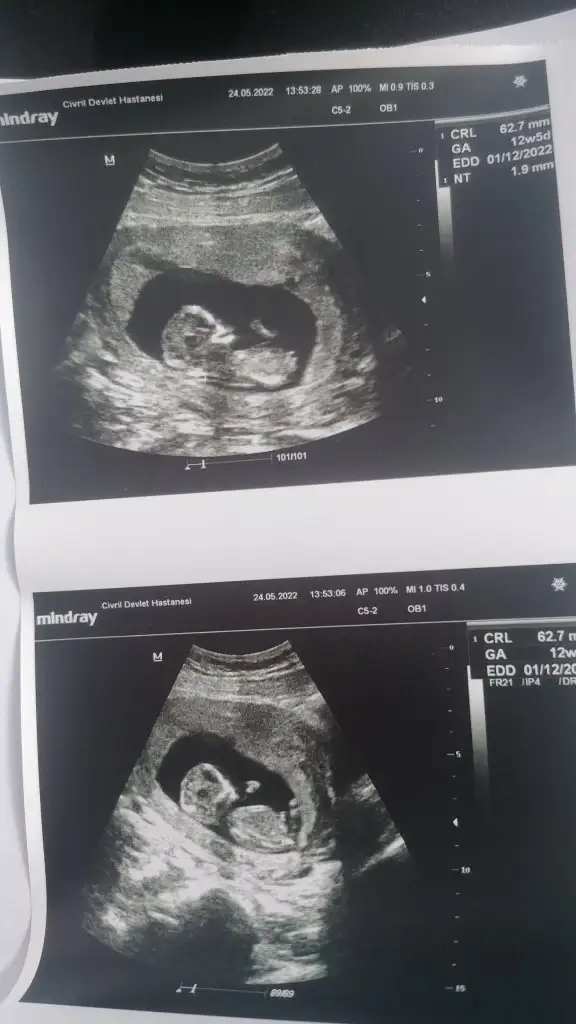

Merhaba ☺️ 12+3 ultrasonumuz bizim için de yorum yapabilir misiniz?

IMG-20220524-WA0004.webp